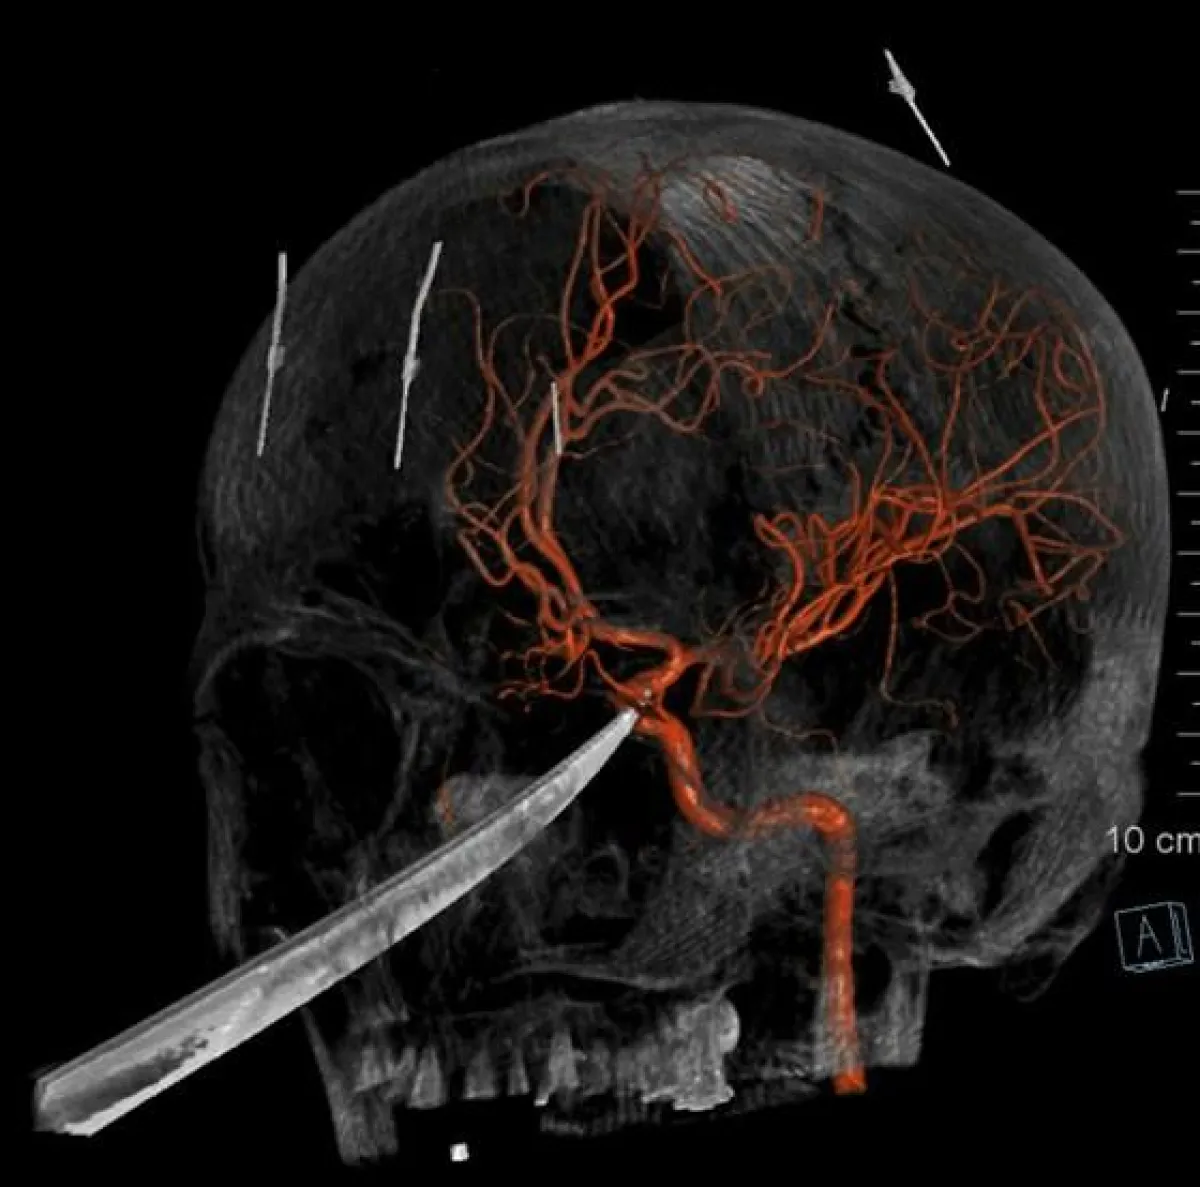

معجزة طبية جديدة، قام بها عدد من الأطباء في ولاية «كانساس» التي تقع في الغرب الأوسط للولايات المتحدة الأمريكية. بعدما تمكنوا بأعجوبة كبيرة من إنقاذ حياة الفتى المراهق «إيلي غريغ»، البالغ من العمر 15 عاماً. والذي كان قد وصل إلى المستشفى وهناك سكين بطول 25 سنتيمتراً يخرج من جمجمته. بحادثة مروعة تعرض لها في الأيام الماضية.

وتابعت «فوكس نيوز»، أنه تم نقل «إيلي»، إلى مستشفى «ميرسي» للأطفال في الولاية. وعلى الفور سارع الأطباء لحظة وصوله إلى إجراء الإسعافات اللازمة له. ولأن الأطباء كانوا قلقين من احتمالية تلف «الشريان السباتي» في دماغ الفتى، مما سيؤدي إلى الإصابة بالسكتة الدماغية أو أضرار جسيمة أخرى في الدماغ. قرروا على الفور نقله إلى النظام الصحي بجامعة كانساس.

وبالفعل تم نقله إلى مستشفى الجامعة، وهناك أمضى الأطباء الساعات الـ24 التالية، في علاج الفتى الأمريكي، وبذلوا كل ما لديهم لإنقاذ حياته. وبالفعل استطاعوا أخيراً إخراج السكين من جمجمته. ويخضع «إيلي» في الوقت الحالي للعلاج بالمضادات الحيوية واللقاح ضد الكزاز الـ«تيتانوس». وعلى جانب آخر، تم تحذيره وتحذير والدته «جيمي راسل» من الاقتراب من أي أدوات حادة على الإطلاق.